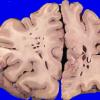

Artifact - Swiss Cheese Brain (2)